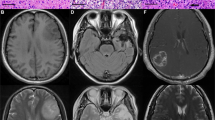

It has been suggested that gliomas are driven by a subpopulation of GSCs. GSCs share similar properties to normal NSCs, and cause xenografts more closely resembling primary gliomas than serum-cultured non-CSCs when injected into brains of immunocompromised mice.30 Our results demonstrate that elevated ZNF217 expression in gliomas is associated with poor prognosis. We further investigated if ZNF217 would be preferentially expressed in GSCs and contribute to the tumorigenicity of gliomas fueled by GSCs. We compared the expressions of ZNF217 in GSCs and non-GSCs. Seven glioma-derived neurosphere cell lines cultured in SFM, which are enriched for stem-like cells,28, 30, 31 were used as GSCs. In addition, 10% serum-cultured primary glioma cells and the GBM cell lines U87, U251 and A172 were used as non-GSCs30 and two normal NSC cell lines from human fetal brains cultured in SFM were used as normal controls. Immunofluorescence and western blotting demonstrated that the GSC markers Nestin, CD15, CD133 and OLIG2 were expressed in GSCs, but non-expressed or lowly expressed in serum-cultured GBM cell lines and primary non-GSCs. This indicates that SFM-cultured glioma spheres were enriched in GSCs, while serum-cultured primary glioma cells and GBM cell lines contained less or no GSCs (Figure 4a and b).

GSCs are enriched in ZNF217 compared with non-GSCs and normal NSCs. (a, b) Representative immunofluorescence images and western blots showing the expression of stem cell markers, Nestin, CD15, CD133 and OLIG2, in NSCs and GSCs, while little or no expression was seen in serum-cultured primary glioma cells and GBM cell lines (U87 and A172). (c, d) ZNF217 expression in normal NSCs, serum-cultured GBM cell lines, non-GSCs and GSCs. ZNF217 is overexpressed in GSCs compared with normal NSCs and non-GSCs. NSCs also expressed slightly higher levels of ZNF217 than non-GSCs. (e) Representative western blots showing that the stem cell marker CD133 was reduced, while the glial marker GFAP was increased in differentiated GSCs. (f) qPCR showing ZNF217 expression was decreased in differentiated GSCs.

qPCR showed that ZNF217 was expressed in both GSCs and normal NSCs, but at higher levels of expression in GSCs (Figure 4c and d). Importantly, both GSCs and NSCs expressed higher levels of ZNF217 than non-GSCs (Figure 4c and d). These results indicate that stem cells, especially GSCs, are enriched in ZNF217. In support of this hypothesis, GSCs were subjected to forced differentiation in 10% serum medium without growth factors for 2 weeks. Western blotting showed that the stem cell marker CD133 was downregulated and glial marker GFAP was upregulated in differentiated GSCs (Figure 4e). Furthermore, qPCR demonstrated that ZNF217 was downregulated in six of the seven GSC cell lines by 36–74% (55±16%) after differentiation (Figure 4f), further supporting the notion that stem-like cells are enriched in ZNF217.